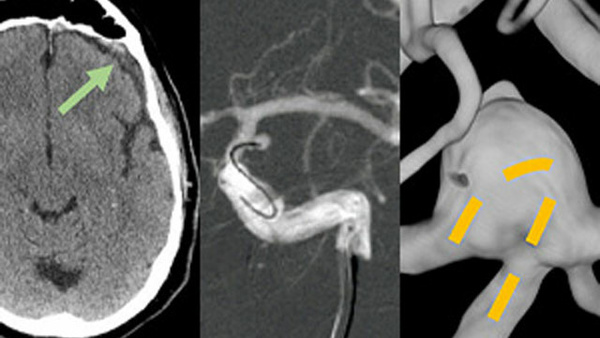

Masterclass #4: I am a bifurcation aneurysm: do I prefer being in a cage or do I prefer being the cage: Y-stenting vs WEB

When we do treat a bifurcation aneurysm, should we be using an external caging technique, such as Y-stenting, or is it better to let the aneurysm itself form the cage, as when an intrasaccular device, the Woven EndoBridge (WEB), is employed?

• How does imaging help us to better understand the relationship of the WEB and the side branches or determining the relationship of the neck of the aneurysm and the WEB device when it is deployed?